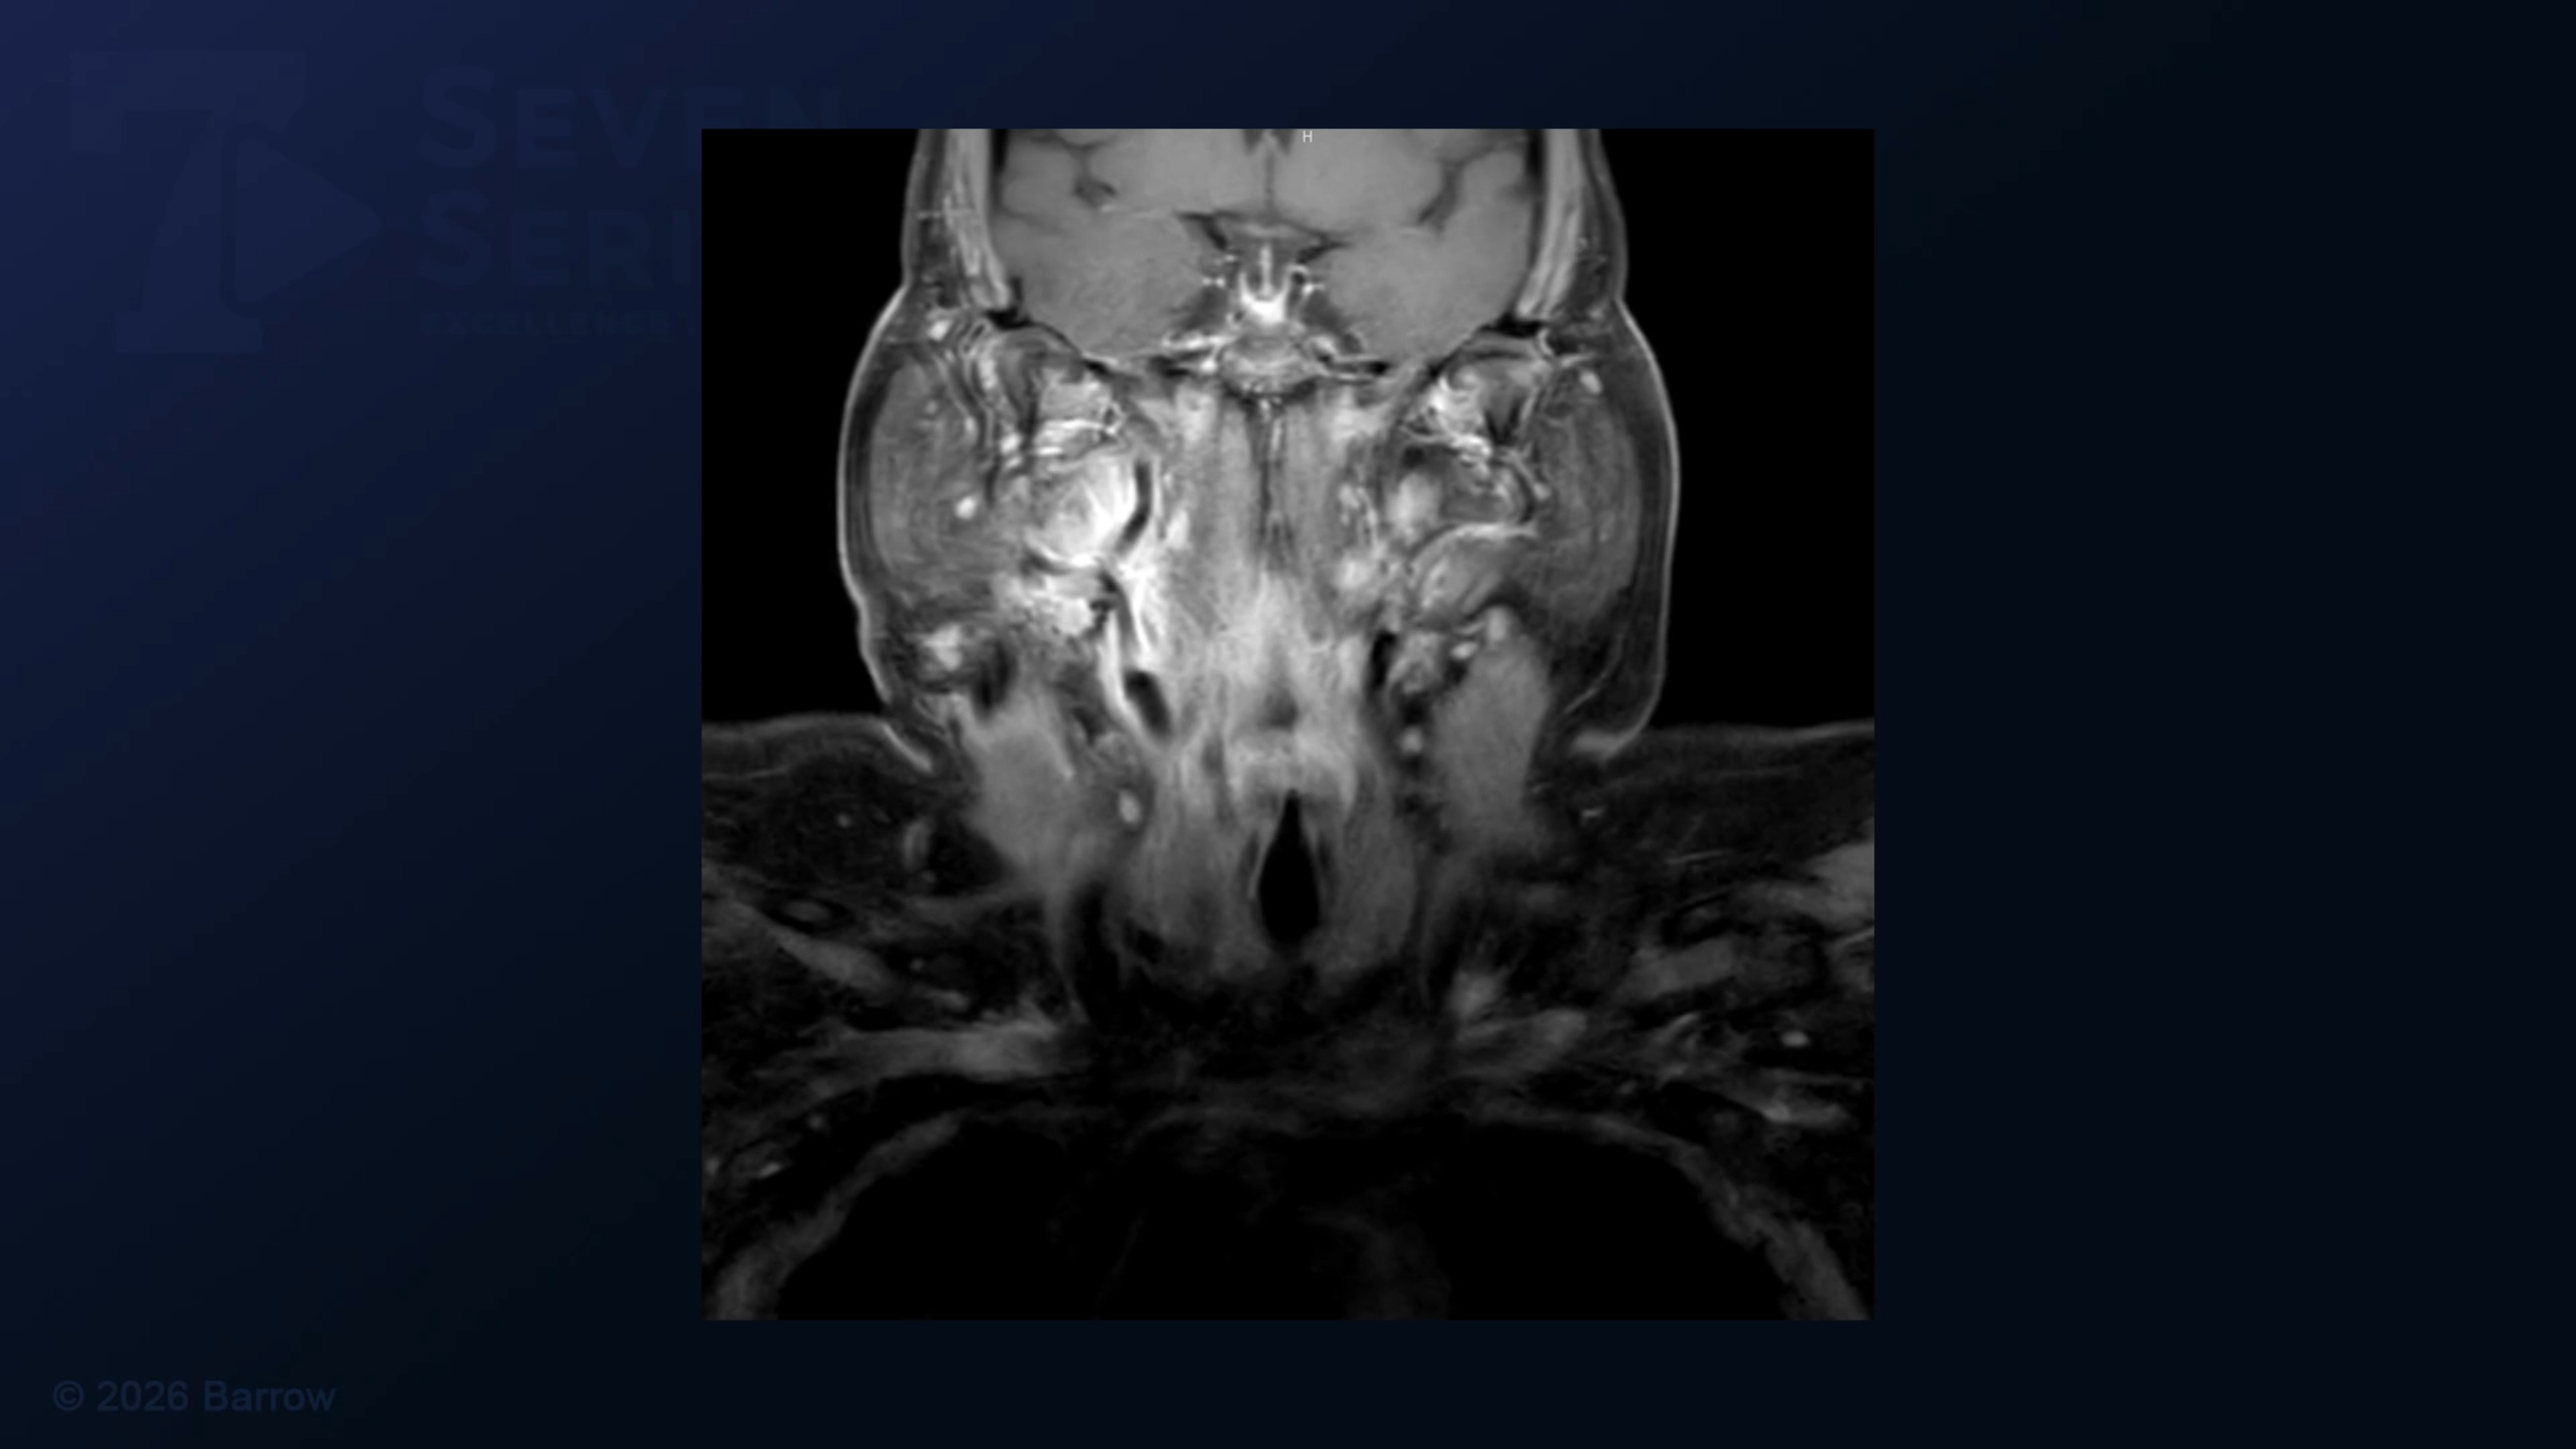

#504: Transcervical Approach for Resection of a Glomus Vagale Tumor

Episode 504 of Seven Series shows a transcervical approach for resection of a glomus vagale tumor.